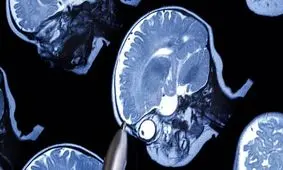

اسکنهای مغزی نشان میدهند که ساختارهای نورون در کودکان مبتلا به اوتیسم متفاوت است.

یک روش جدید مبتنی بر تصویربرداری MRI موسوم به DT-MRI با کمک هوش مصنوعی، ارتباطات غیرطبیعی مانند اختلال در ارتباطات…